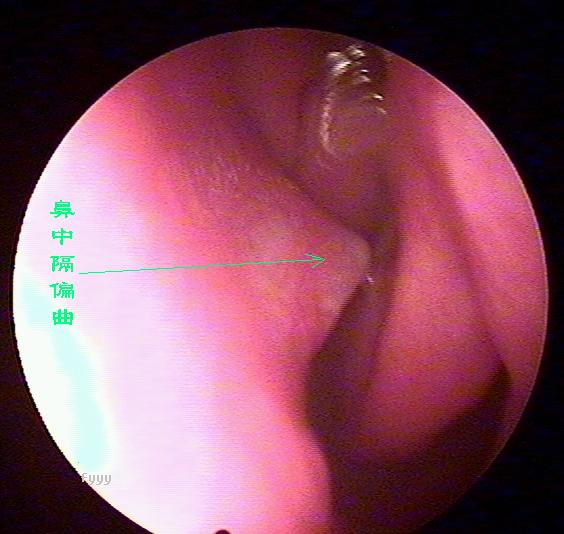

经常流鼻血是鼻中隔偏曲惹的祸

老流鼻血可能是鼻中隔偏曲惹的祸,鼻中隔偏曲部位经常会出现血管畸形,而且这里的粘膜也相对较薄,受气流、尘埃等刺激后容易破损、出血,主要症状为:交替性或持续性鼻塞,头痛,鼻出血及流脓涕等。且难以痊愈,经常发作。西安新城中大耳鼻喉医院耳鼻喉科推出的,快速无痛治疗鼻中隔偏曲。

2、鼻出血:鼻出血是鼻中隔偏曲较为常见的症状之一。发生在偏曲之凸面、骨棘或骨嵴的先进部,此处粘膜薄。常受气流和尘埃刺激易发生糜烂而出血。老是在洗脸的时候流鼻血是什么原因 ?

鼻中隔偏曲的诊断检查

鼻中隔偏曲进行鼻内检查以判断鼻中隔偏曲的类型和程度,注意鉴别鼻中隔粘膜肥厚和是否同时存在鼻内其它疾病,如原发病变—肿瘤、异物或继发病变—鼻窦炎、息肉等。 另一罕见者为鼻中隔梅毒瘤,其质地中亦较硬,但该处粘膜明显充血。